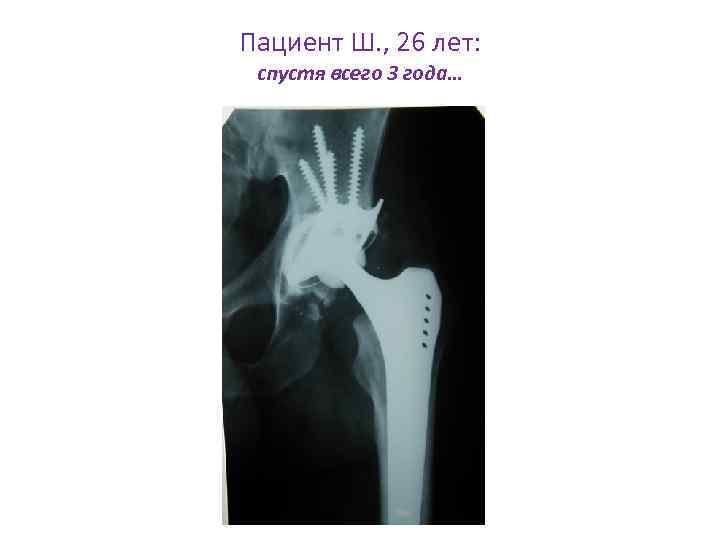

Пациент Ш. , 26 лет: Через 3 года от начала заболевания (артрит, уретрит, конъюнктивит)

Пациент Ш. , 26 лет: спустя всего 3 года…